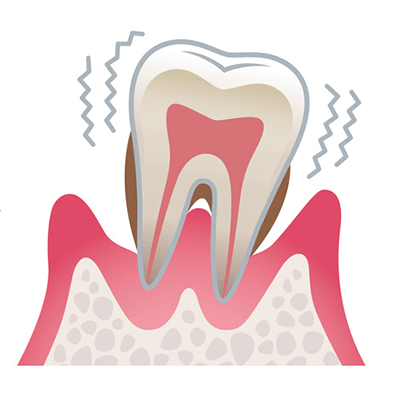

重度歯周病

歯を支える骨が大きく失われ、歯ぐきの炎症が強くなった状態です。歯が大きくグラつき、歯根が見えるようになります。膿が出たり、口臭が強くなったりし、放っておくと歯が抜け落ちることもあります。

見た目の特徴

歯ぐきは赤紫色に変化し、さらに腫れが強くなります。歯と歯のすき間が広がり、食べ物が詰まりやすくなります。